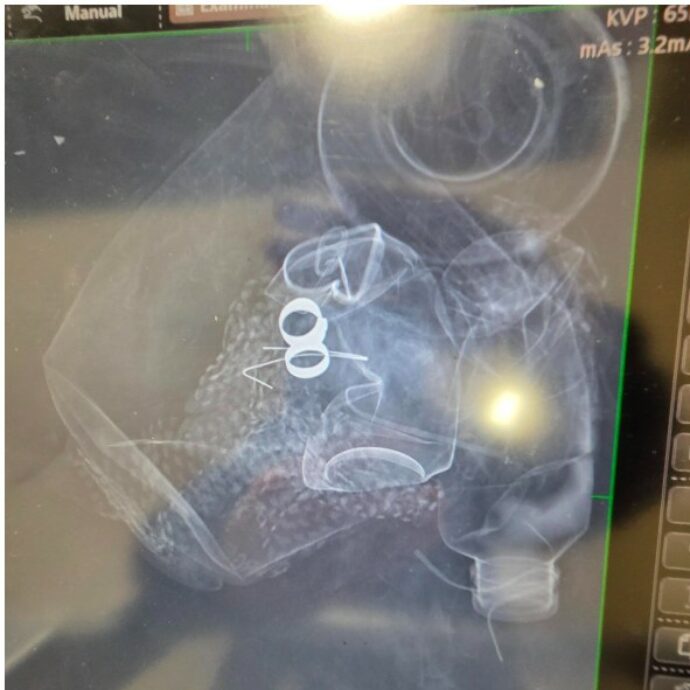

Un uomo di 38 anni di St Neots, nel Cambridgeshire, è morto a fine settembre dopo aver scoperto che i dolori alla schiena, inizialmente attribuiti all’età, erano causati da un tumore al retto. Steve Burrows aveva iniziato ad avvertire fastidi a fine luglio e, non trovando sollievo, si era recato al pronto soccorso dove gli esami avevano evidenziato la presenza di un cancro. Successivi accertamenti avevano poi confermato che la malattia era già al quarto stadio.

Burrows soffriva di Poliposi Adenomatosa Familiare (FAP), una patologia ereditaria che provoca la formazione di polipi intestinali e aumenta il rischio di tumori. Gli era stata diagnosticata da bambino e a 13 anni era stato sottoposto a un intervento chirurgico per la rimozione di parte del retto.